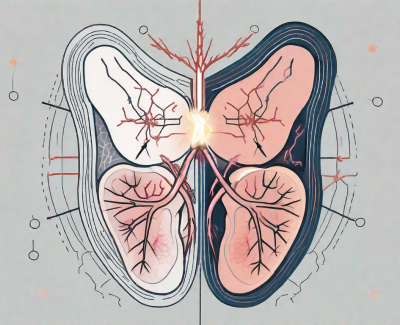

Troubles de la circulation